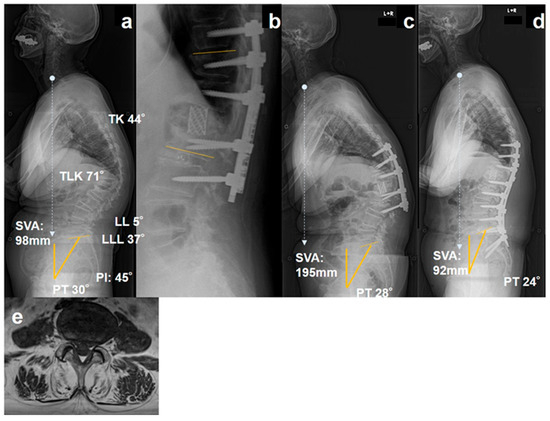

25 February 2026

Background: Kyphotic deformity following osteoporotic vertebral fracture (KDOVF) often requires corrective surgery to restore sagittal alignment; however, mechanical complications, such as proximal junctional failure (PJF) and distal junctional failu...